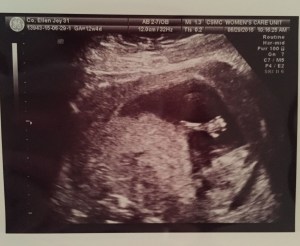

All for the love of our little peanut. Here’s our little one’s first pic at 4 weeks. Merely a dot but this little sac meant the world to us.

We had to do weekly ultrasound as my OB wanted to monitor every little thing to ensure all goes well. At 5 weeks, after my LIT & IVIG, the subchorionic hemorrhage cleared up. Thank God.

Thankfully, each week would show us our baby’s milestones. Milestones that would ease our fears and calm our hearts. Milestones that would assure us that our little one is fighting to be with us all the way ❤

At 8 weeks, its heart was beating 158 bpm strong. There was also another sac seen and our doctors first thought it might be twins. But the other vanished a week later and might have just been another subchorionic.

At 9 weeks, we saw our baby more active and heard its heartbeat for the first time! I cried at the comforting sound of our little one’s strong heartbeat! So thankful for the doctors at Cardinal Santos where I continued my weekly ultrasound. They are very thorough and I can take pictures and videos of our baby’s milestones weekly. Here’s a video of our little love at 9 weeks.

We battled with subchorionic hemorrhage throughout the first semester. On some weeks it would clear up, then another week there’d be a new one. Thankfully, our little one is a fighter. The doctors would tell us not to worry as our baby is continuing to grow healthier and bigger each week, completely disregarding it. As the baby grew, the spots of hemorrhage decreased until it was no longer significant. I told Ken one time that I think our own little one is assuring me on her own. I think it knows that I’ve been worrying about her safety since day 1. As for each week that I’d see our baby, it would always make strong movements as if to say “Mommy, it’s okay. Breathe, relax, I’m doing okay. Everything is okay, Mom!”

At 12 weeks, the cutie little nose was already seen! Our little love was checked for the nuchal translucency and others and all came out normal and healthy! 🙂

When Ken entered the room, our little one raised his arm and waved as if to say “Hi Daddddddddy!!!” 🙂

Here’s a video of our baby at 12 weeks.